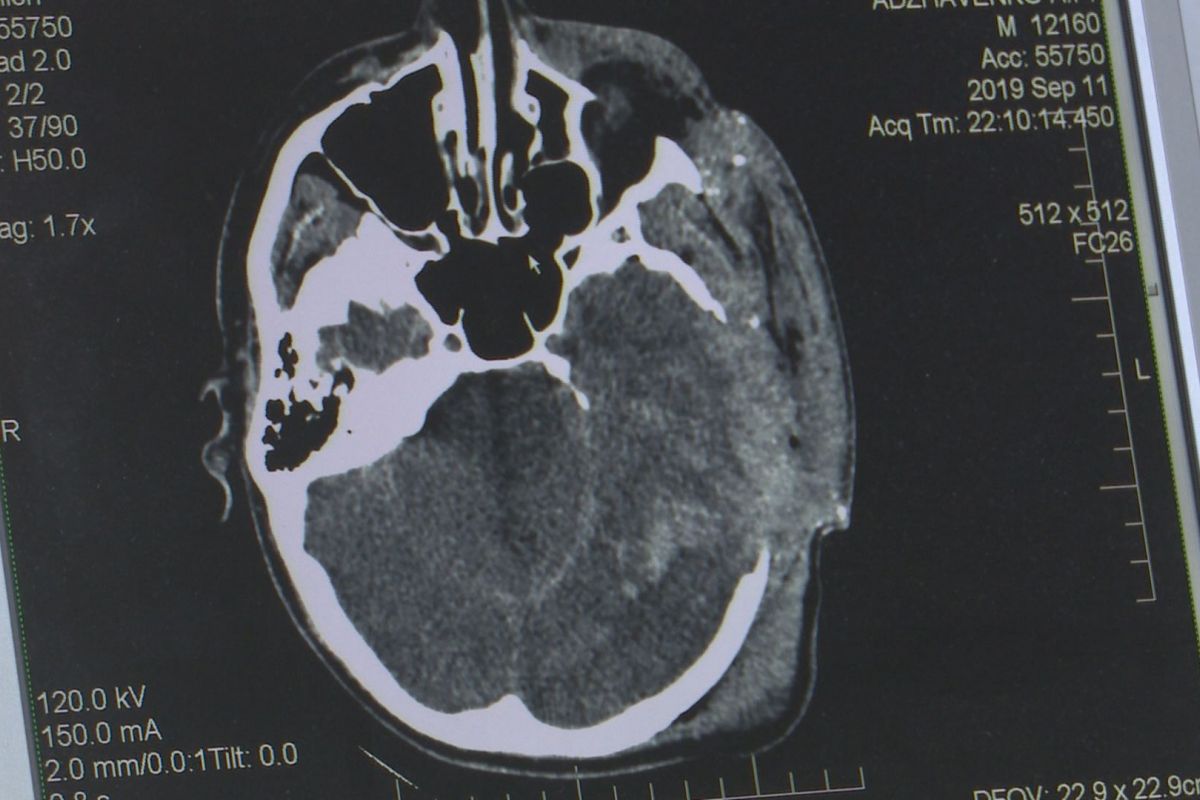

Куля пройшла під оком та вилетіла через скроневу кістку. Із таким важким пораненням ввечері 11 вересня до обласної лікарні імені Мечникова доставили АТОвця.

Аби врятувати хлопцеві життя, медики перелили більш ніж літр крові та зробили складну операцію. Пораненому військовому 24 роки, він – старший сержант.

Лікарі припускають, такі травми – наслідок вогнепального снайперського поранення.